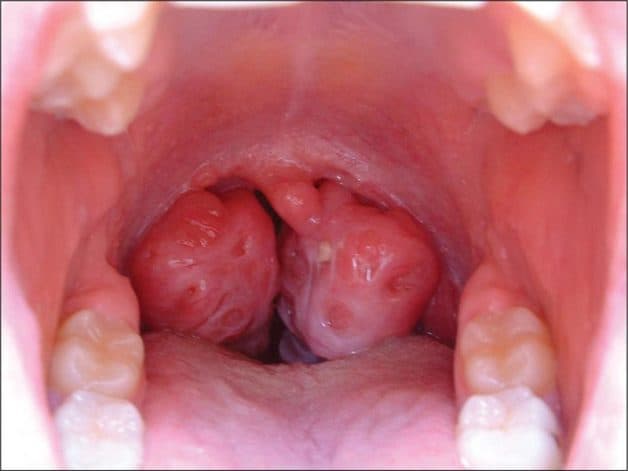

Amidan là một tổ chức với nhiệm vụ bảo vệ cơ thể chống lại sự xâm nhập của vi khuẩn xâm nhập vào qua đường vòm họng. Tuy nhiên, nếu tác nhân có hại tấn công cơ thể với số lượng lớn thì hiện tượng viêm Amidan sẽ xảy ra. Vậy khi nào cần cắt Amidan?

– Kích thước Amidan quá to, khiến cho đường thở bị bít tắc và gây khó thở.

– Cấu trúc Amidan của bệnh nhân có nhiều ngóc ngách chứa chất gây nên tình trạng hôi miệng, tiềm ẩn vi khuẩn tại Amidan sinh sôi và phát triển.

Amidan quá phát khiến cho đường thở bị bít tắc và gây nên hiện tượng ngưng thở